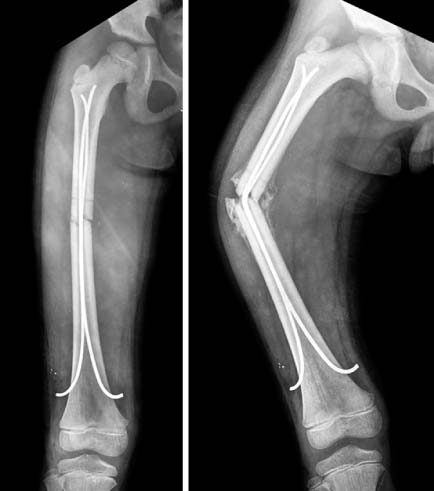

Fig. 1

A femoral shaft fracture with a butterfly fragment in 11 years-old girl.

Fig. 1 A femoral shaft fracture with a butterfly fragment in 11 years-old girl.